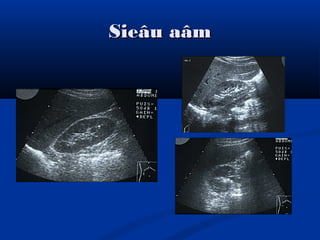

Siêu âmSiêu âm

Sieâu aâmSieâu aâm

Hình aûnh bình thöôøngHình aûnh bình thöôøng